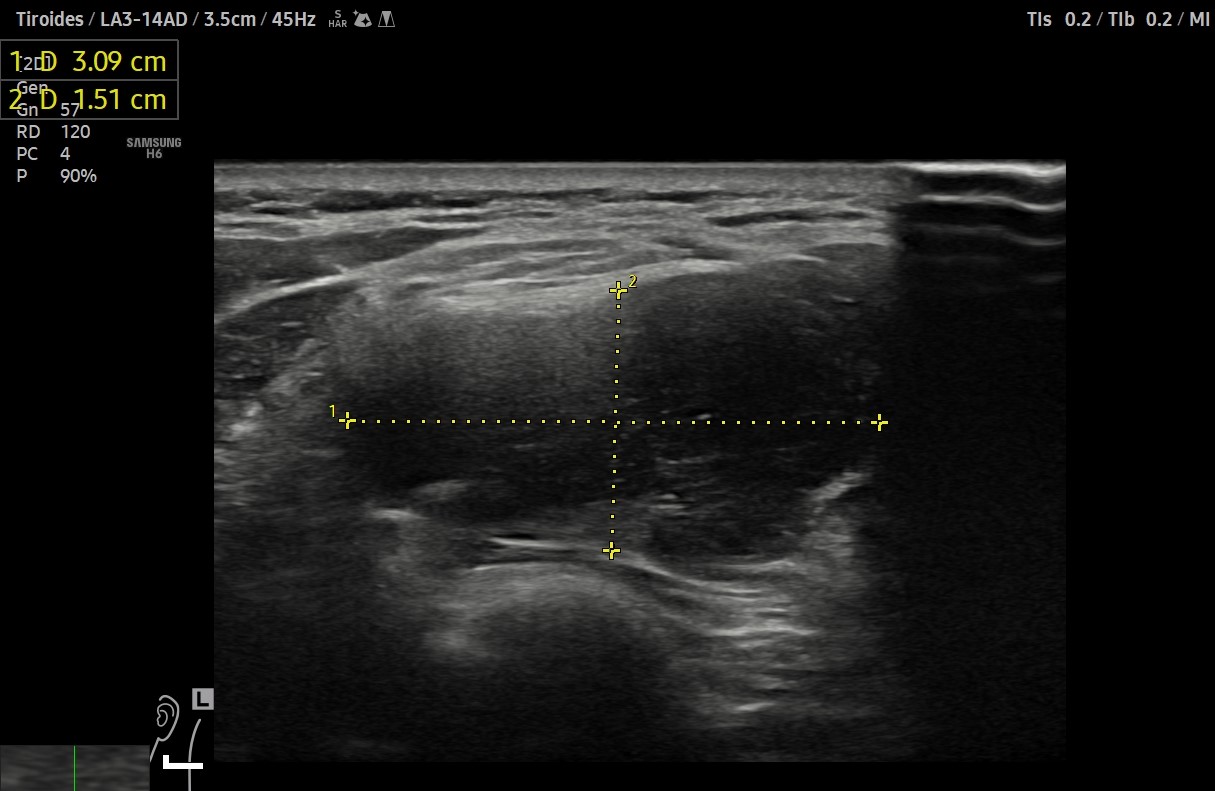

Ante sospecha clínica de malignidad se realiza ecografía.

Hallazgos ecográficos

Ecografía clínica de cuello: objetivando en cara lateral izquierda una imagen hipoecogénica, lobulada, heterogénea y vascularizada al Doppler, de aproximadamente de 3 cm, con apariencia de depender de la capa muscular. Adicionalmente, se detectó un nódulo tiroideo izquierdo con microcalcificaciones, aunque la TSH era normal.